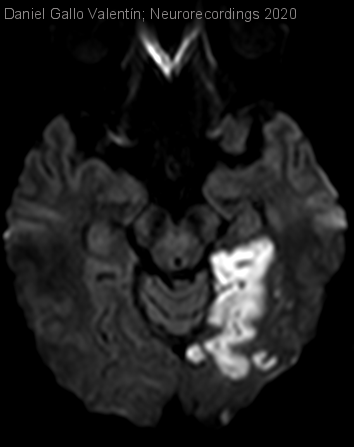

Diagnóstico final: Amnesia isquémica debida a ictus en múltiples territorios vasculares en contexto de endocarditis marántica

Varón de 46 años con antecedentes de hipertensión arterial y síndrome de Lynch con adenocarcinoma de sigma tratado mediante sigmoidectomía y quimioterapia adyuvante. El paciente, que presenta febrícula vespertina de un mes de evolución sin...